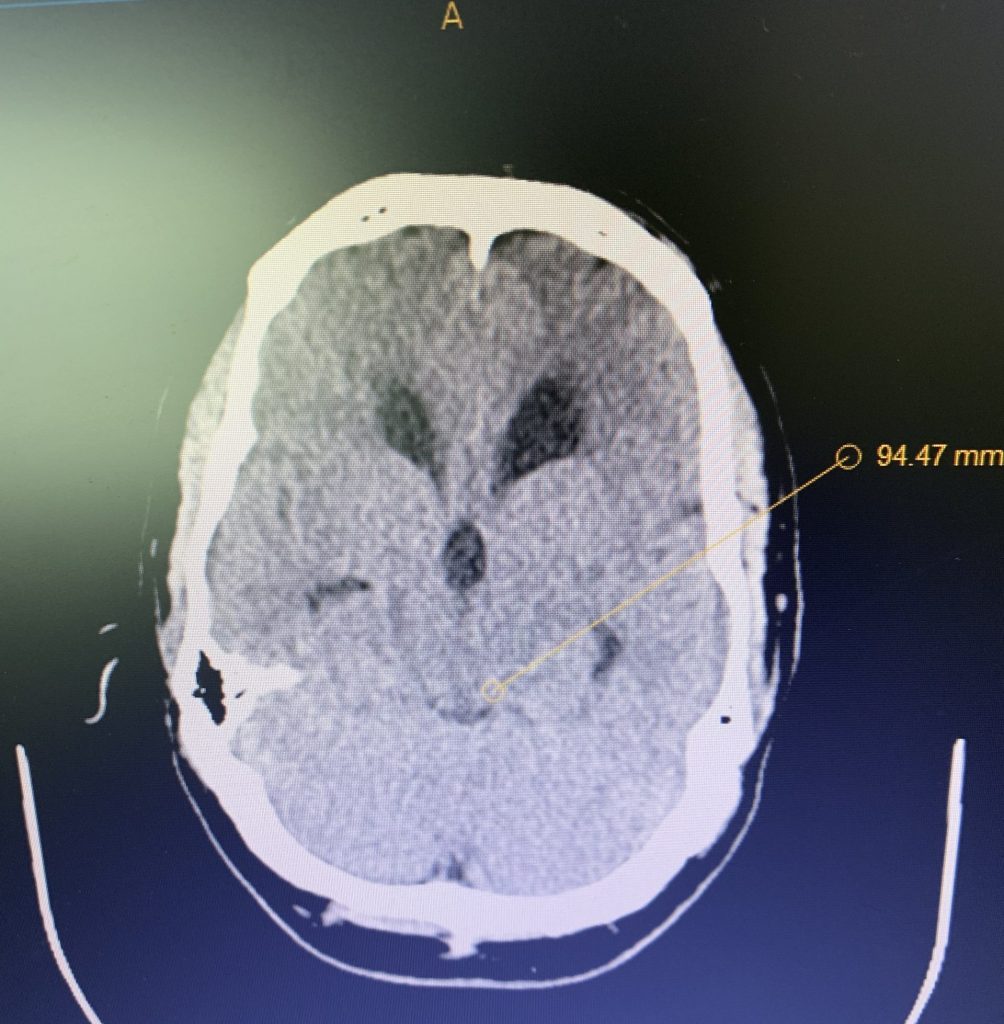

Figure 1B,C: Pre-operative CT images.

Prior to shunting, a head CT was obtained and the head CT in addition to documenting a patten of obstructive hydrocephalus suggested a possible mass lesion compressing the aqueduct at its inferior aspect. Figure #1 demonstrates the hydrocephalus and the possible lesion. A decision was made at this point that the patient had obstructive hydrocephalus that was now symptomatic and he was taken for a laparoscopic-assisted ventriculoperitoneal shunt.